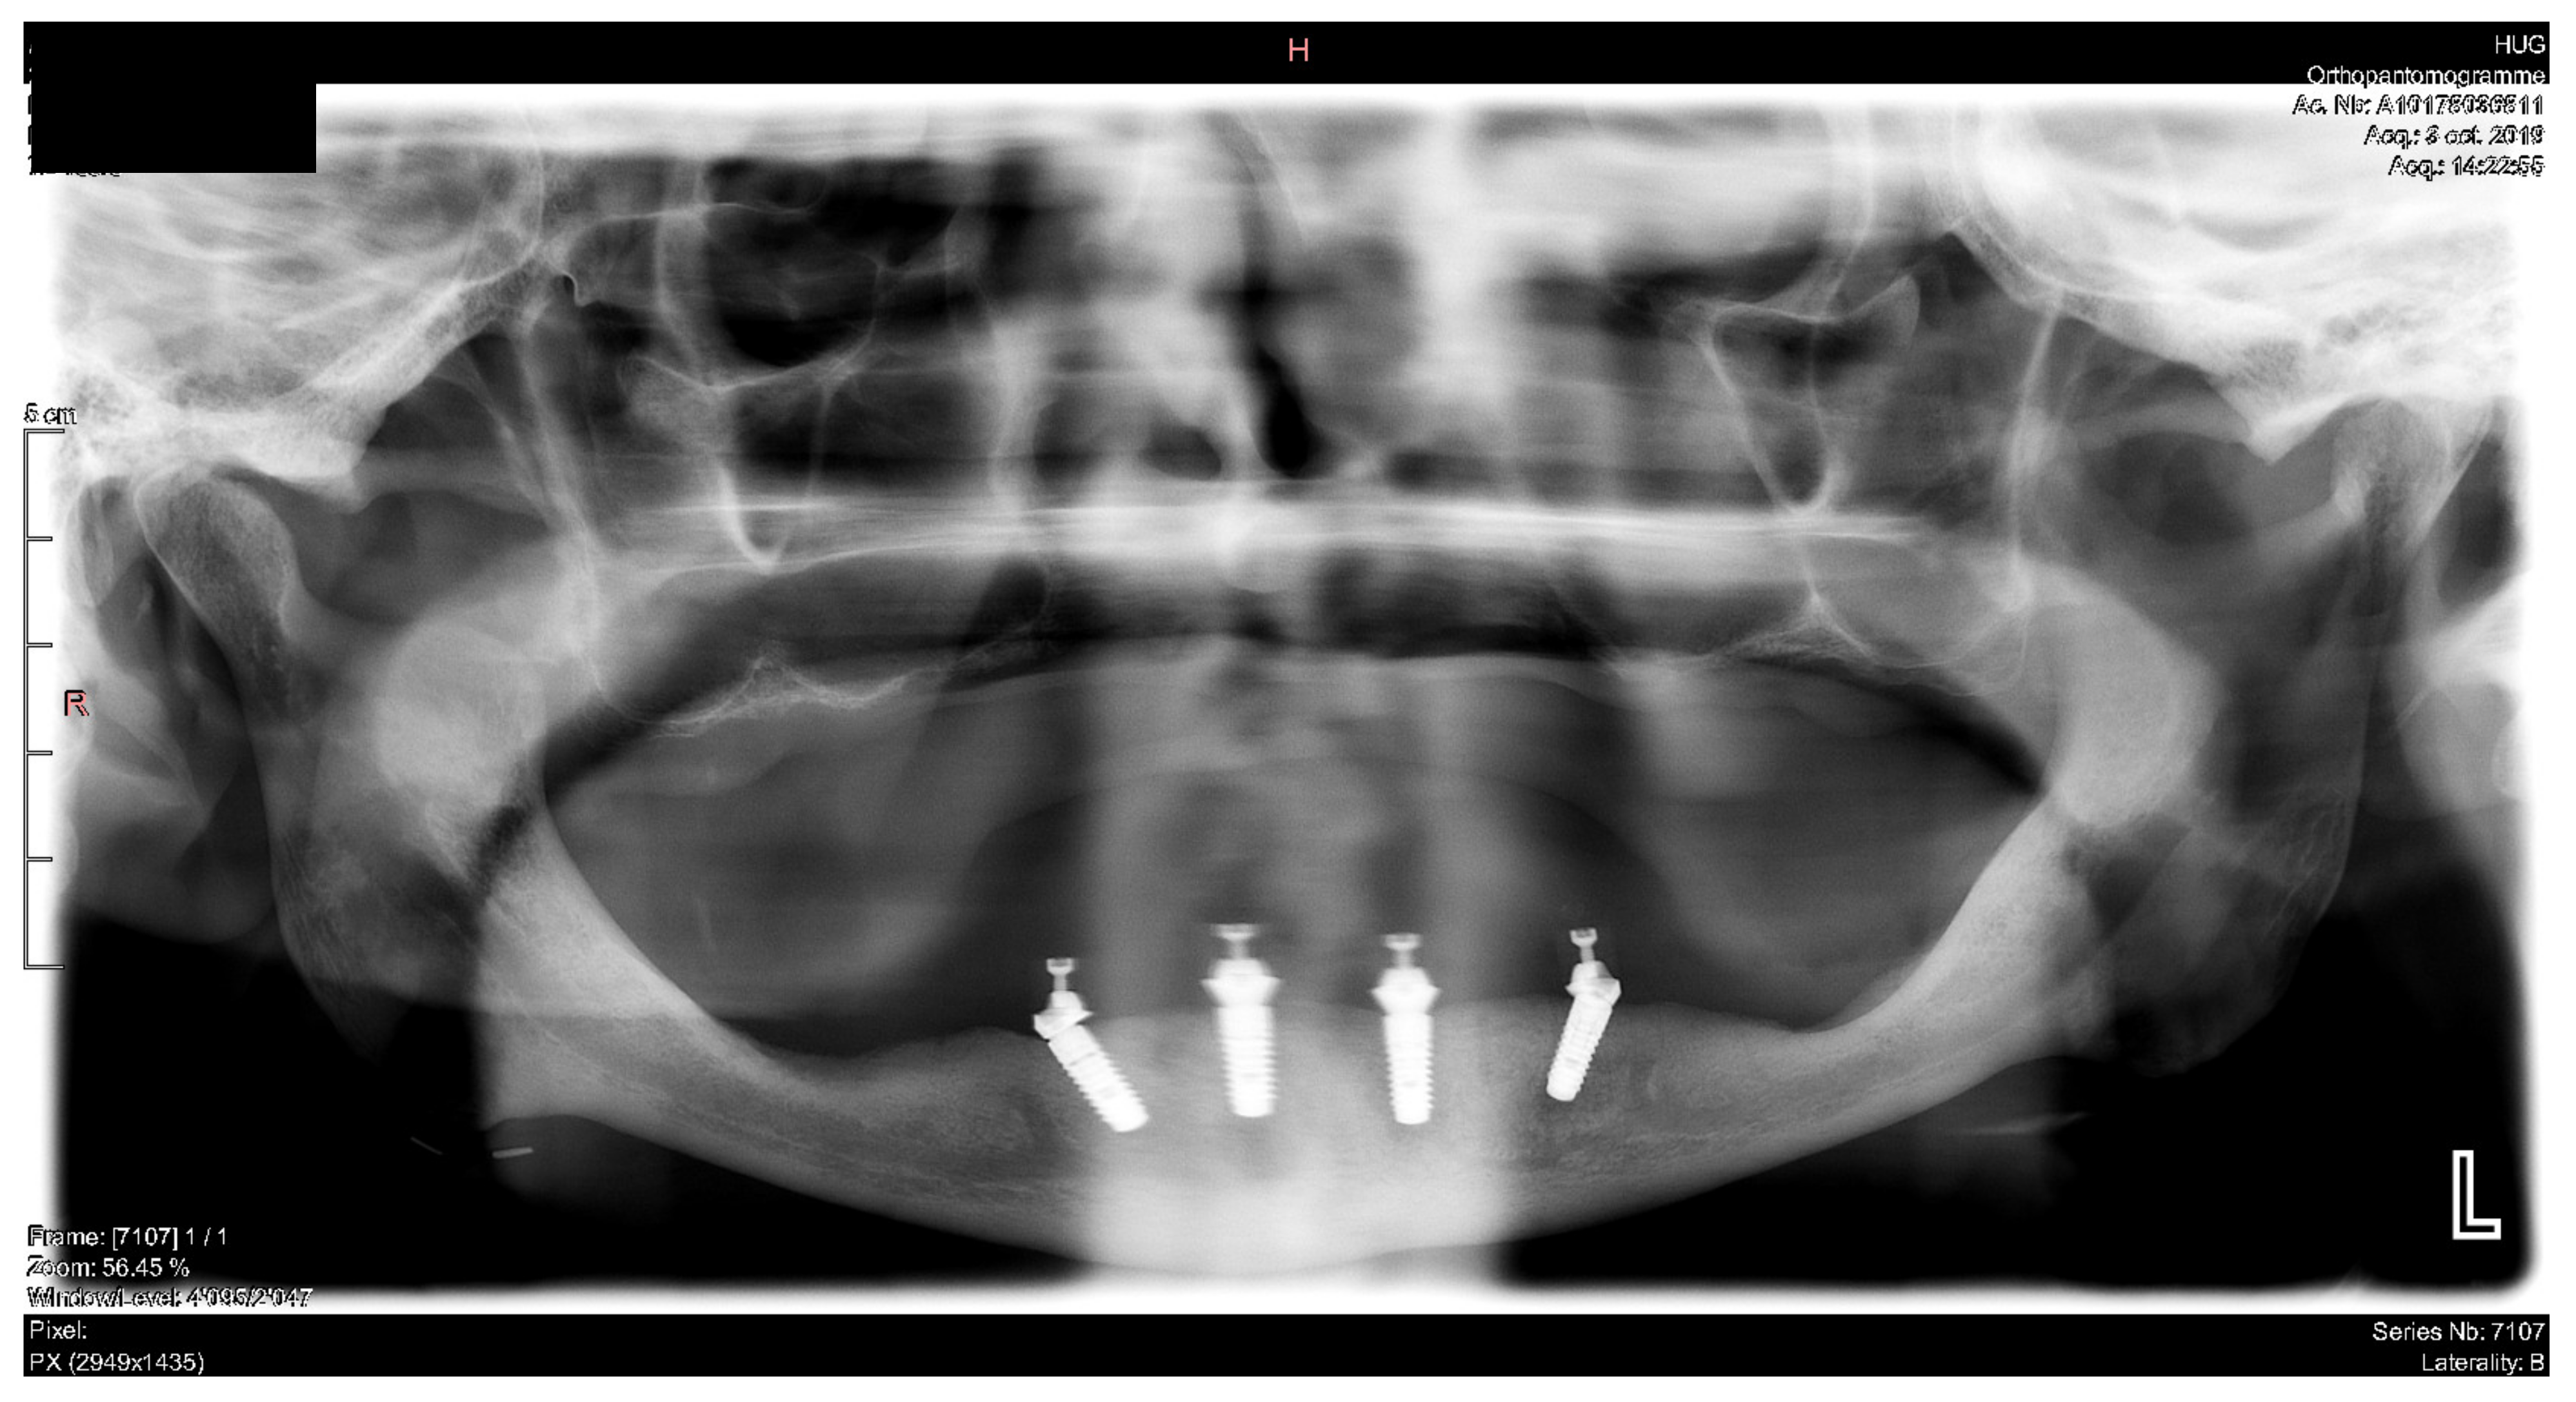

Figure 29.

Panoramic radiograph showing the dental implants in place.